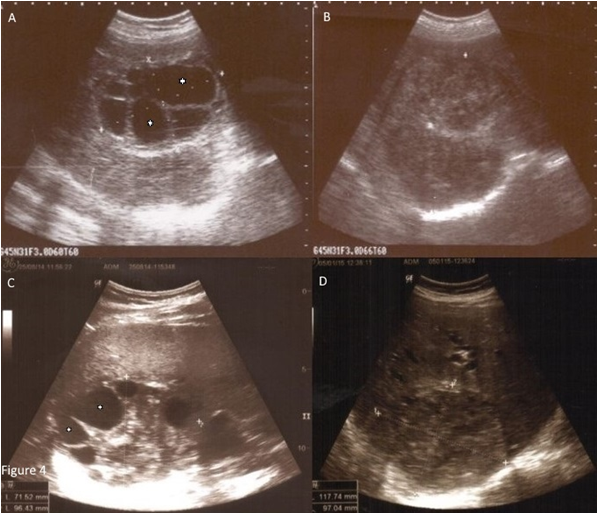

Figure 4 (A) A large multi-septated cystic lesion (stage CE Type 2 B according to WHO classification). Multipl daughter cysts (asterisks) are seen as large multi-septated cystic lesion in the right lobe of liver. It represents as ‘honeycomb’ aspect.

(B) After treatment, the cystic feature of the lesion has disappeared and it is observed in solid form.

(C) The daughter cysts within a solid matrix (stage CE Type 3 B according to WHO classification).

The heterogeneous lesion with cystic components is observed in the liver before treatment. The solid matrix is in centrally and daughter cysts (asterisks) in periphery of the lesion are found.

(D) After the treatment fluid content has totally disappeared. The lesion is seen as solid, like pseudotumor.

The patients were evaluated by detachment, perforating and color changing of the germinative membrane, reduction of cyst volume; degeneration, solidification and calcification of the cysts on the ultrasound examination during and one day after the procedure. The germinative membrane of some of the cysts (46.7%) was detached from the cyst wall, became white, were torn apart and went to pieces down in the type of CE 1 and CE 3A (Figure 3) at the time of the treatment. The CE 2b, 2c and 3B cysts degenerated, changed color and some of the germinative membrane of daughter cysts were detached. They became smaller (87.7%) and 21 (3.9%) of the cysts disappeared. They solidified (91.0%) and calcified (15.4%) during the follow-up (Figures 4). Interestingly, 47 cysts in 36 patients were affected by the treatment of another cyst. They resulted in degeneration and they finally died (Figure 5). Blood samples were collected to check CBC, sedimentation rate, ALT; AST, alkaline phosphatase, GGT and bilirubin before and after the procedure for all patients. The mean follow-up time was 51.24±62.99 (minimum 3.00, maximum 340.00) months. The treatment was effective. (Table 1) When the treatment was not efficient on the first puncture, a second [-n=53(9.9%)], third [-n=8(1.5%)-] and fourth puncture [-n=2(0.4%)-] were applied during the follow-up. Forty-seven (9.91%) out of 474 patients applied to us with several complications before the treatment due to HD. Of 474 patients, 42 (8.86%) had some complications after the treatment. (Tables 2 & 3)